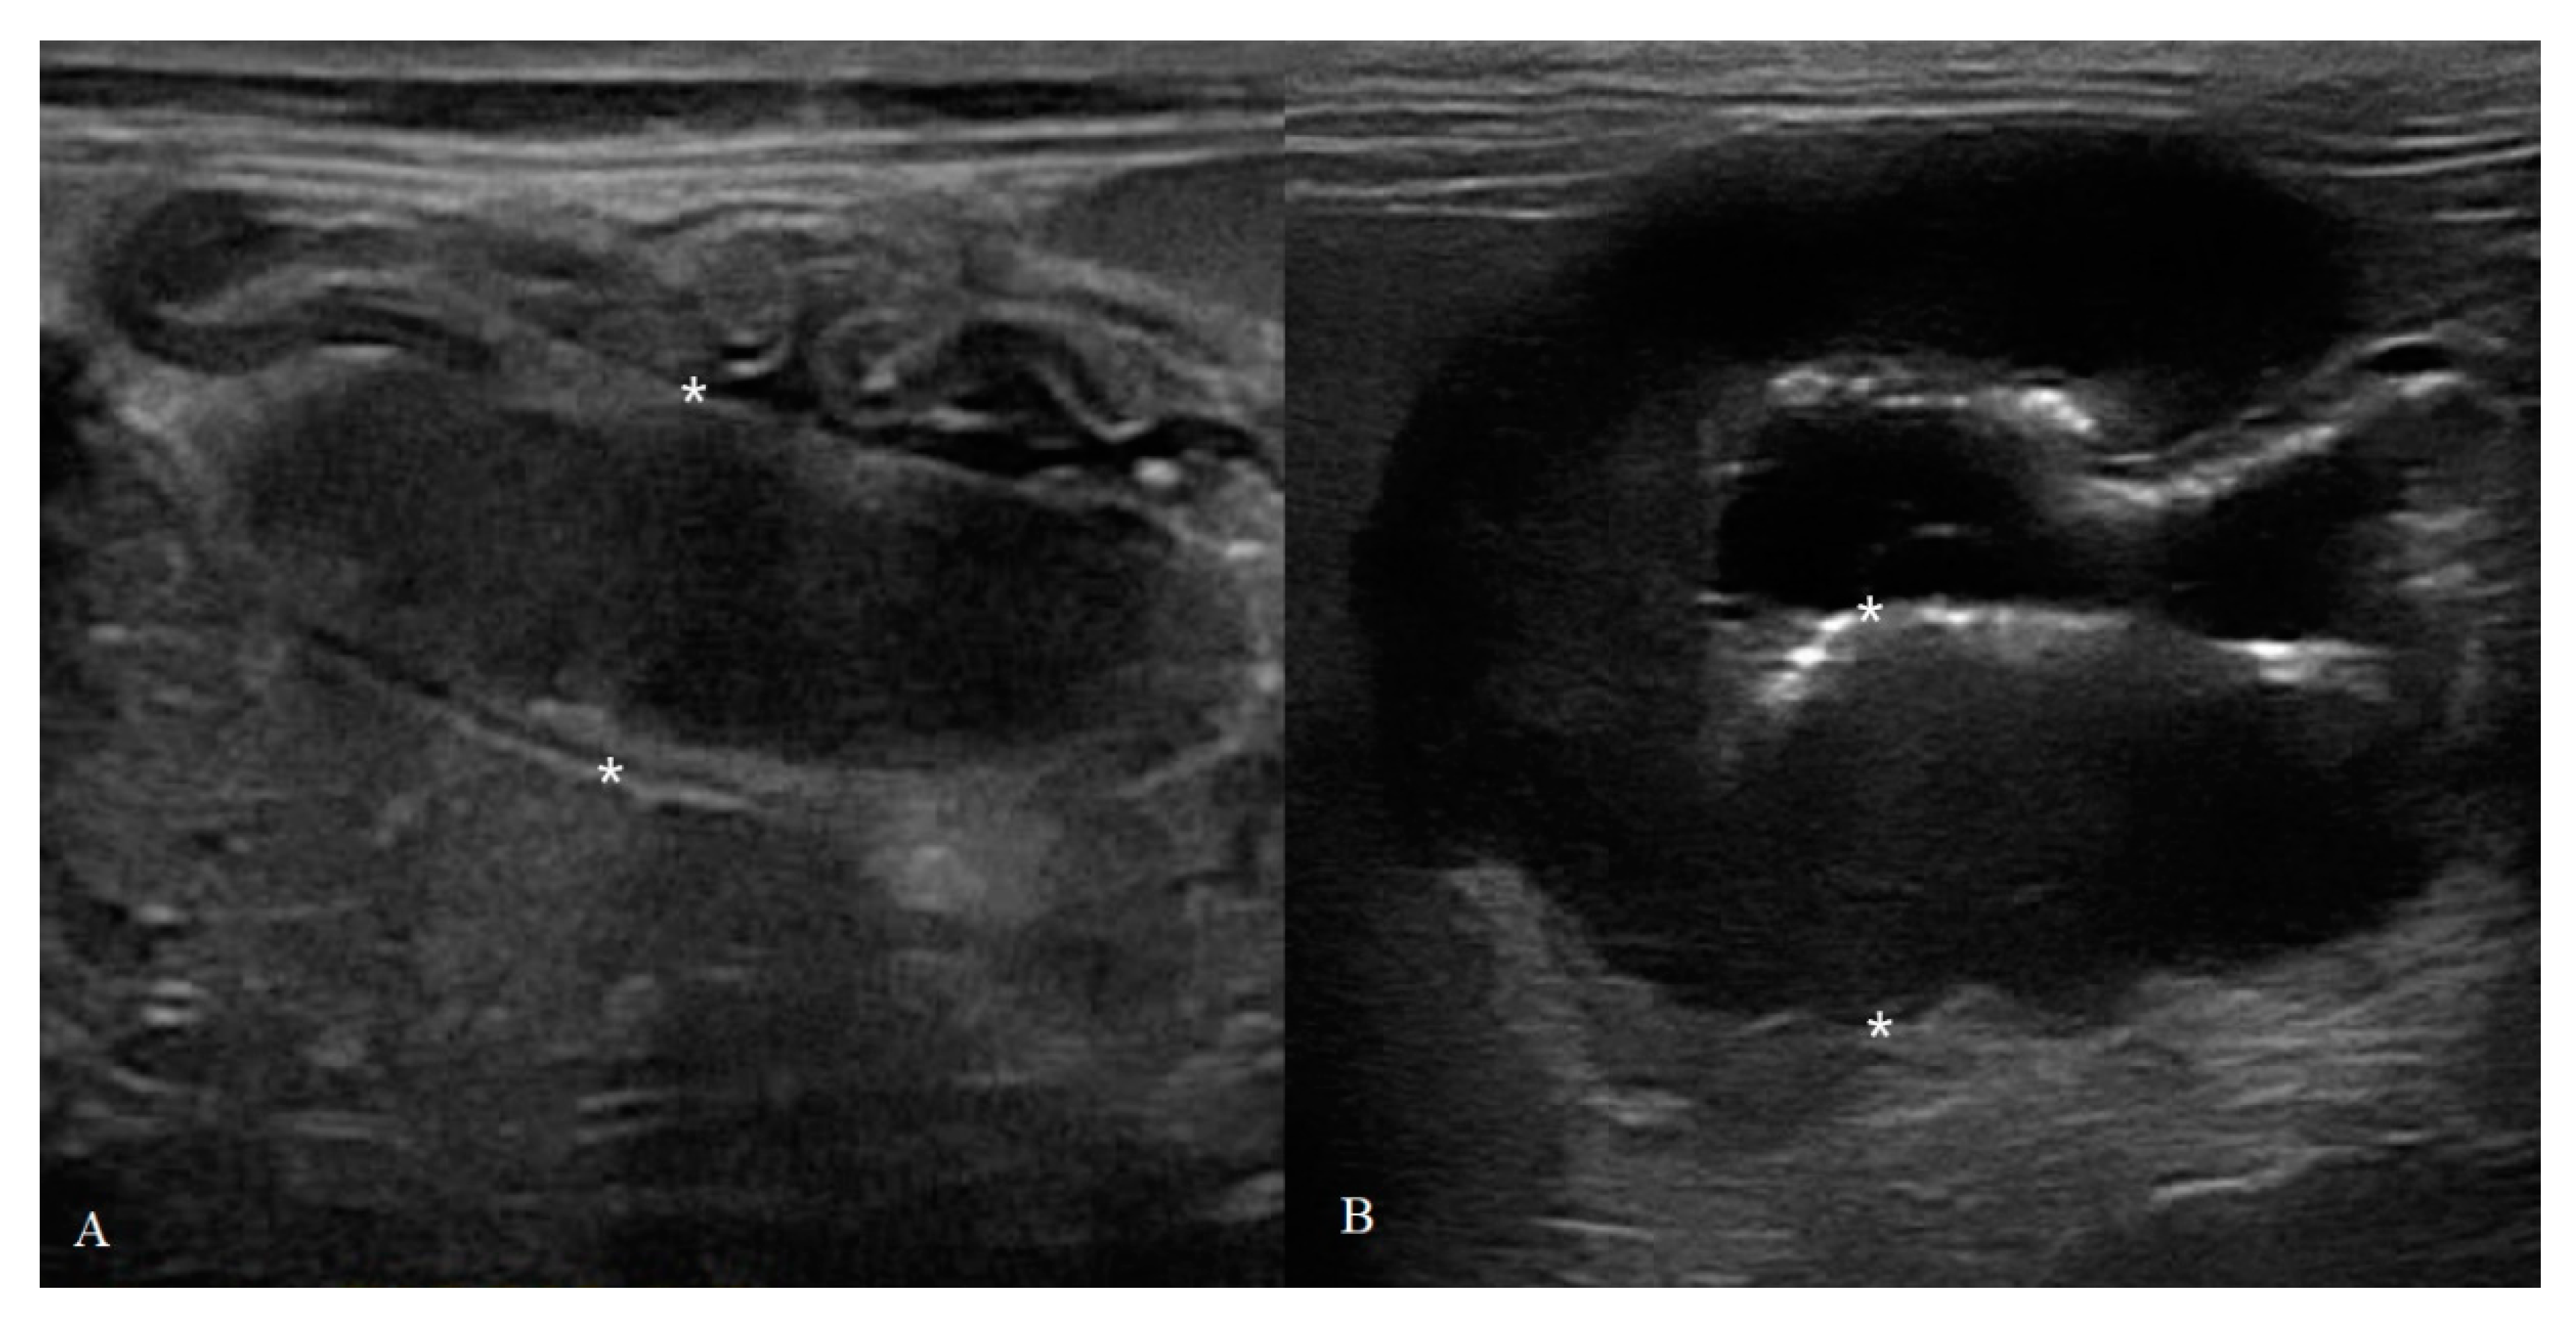

Animals Free FullText BMode and Contrast Enhanced Ultrasonography

From www.mdpi.com

Animals Free FullText BMode and Contrast Enhanced Ultrasonography Cat Intestinal Adenocarcinoma Adc and lsa are the most common large intestinal tumors in cats. Small intestine and particularly jejunum or ileum. Other large intestinal tumors include mct, hsa, and neuroendocrine carcinoma. Adenocarcinomas in cats are a large group of malignant tumors, caused by unregulated cell growth within glandular tissue. Intestinal adenocarcinoma is the second most common alimentary neoplasm in cats, following lymphoma,. Cat Intestinal Adenocarcinoma.